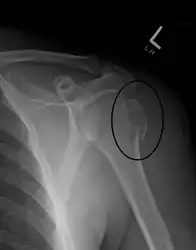

Midshaft humerus fracture with callus formation

Closed shaft fracture in the middle of humerus